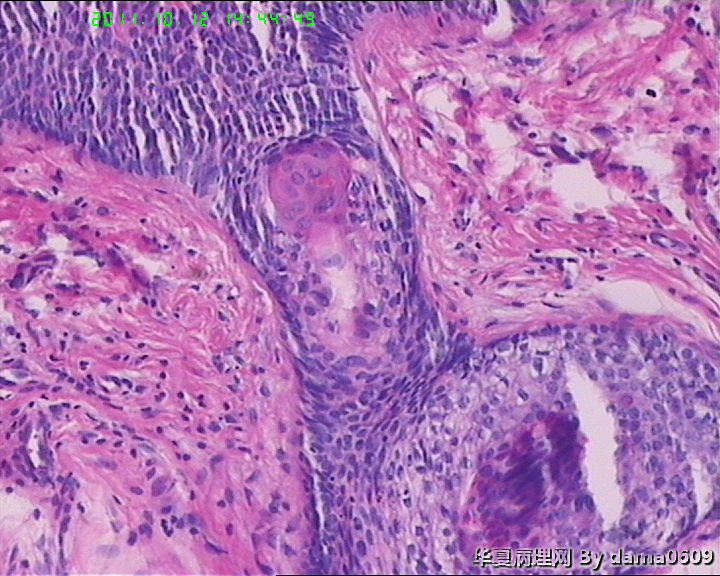

女,42岁,右眼外上方皮下肿物4年。

送检:椭圆形肿物,v:0.5x0.5x0.4cm,实性,灰白色,质软。

毛发腺瘤

诊断考虑毛发腺瘤。病理改变中可见增生的肿瘤细胞团块介于毛发上皮瘤和毛囊瘤之间。可见毛囊漏斗部形成的角质囊肿改变,也可以钙化。